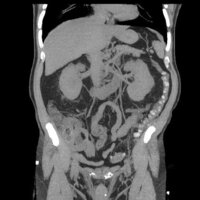

腸の中はピンク色できれいだったが ポリープは白い粒のように見えた 手術の方法など詳しく聞いた上で 別の日に改めて内視鏡で切ってもらった 大腸 がん検診の語り